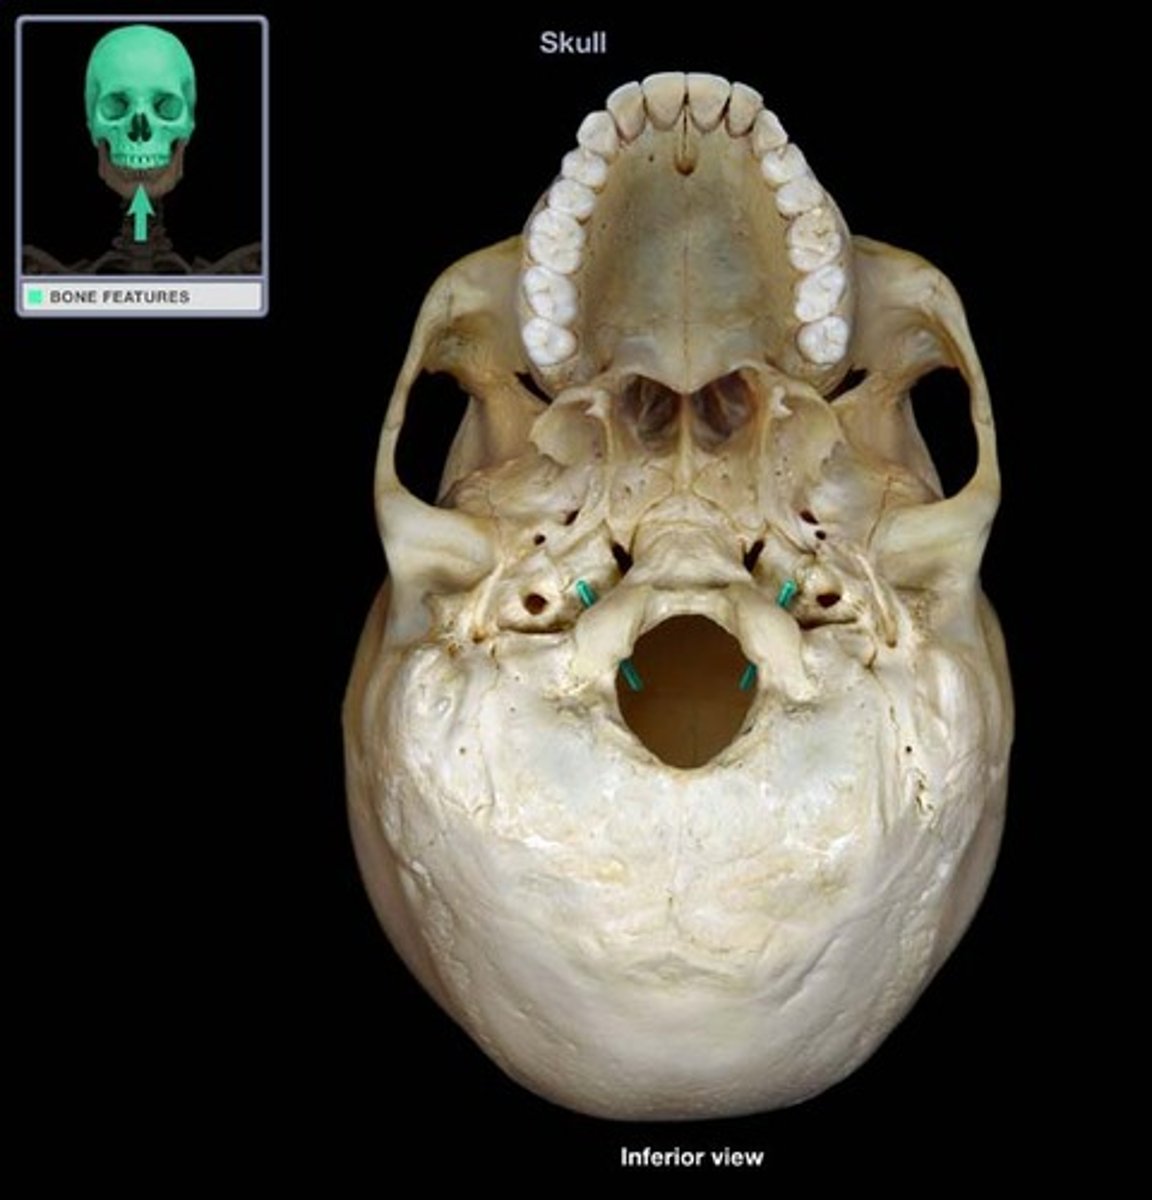

Jugular foramen

Carotid canal

Occipital condyles

Foramen magnum

Hypoglossal canal